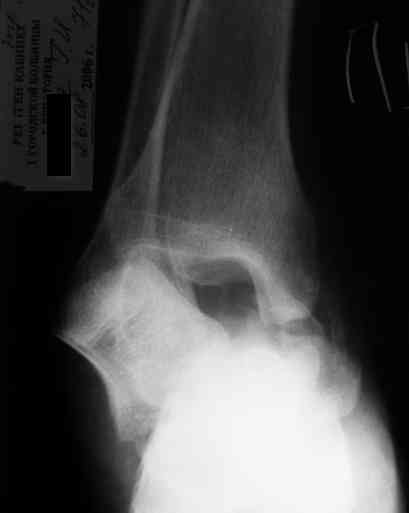

Последний снимок

Мнение по поводу тарана? АН есть?

> Мнение по поводу тарана? АН есть?

Типичная картина некроза.

> Операцию планируем на пятницу. План заведующего - двухсуставной

> артродез АВФ. Скину если получится фото и послеоперационные Р-граммы.

На мой взгляд, у больного асептический некроз таранной кости, осложненный гнойным артритом голеностопного сустава (по снимку не понятно, что это - фистулография или простая рентгенограмма). Оптимален артродез голеностопного сустава, объем резекции таранной кости определится только интраоперационно. Большая проблема - метод фиксации. Работая, в основном, с пациентами пожилого и старческого возраста могу сказать, что ЧКОС они переносят плохо. Адекватный уход за аппаратом возможен только в условиях стационара. Возможность самостоятельной работы с аппаратом, например для ликвидации укорочения, крайне сомнительна. Кроме того, укорочение 3 см (до 5 см) у данной категории больных легче компенсировать ортопедической обувью. К сожалению и фиксирующие повязки (гипсовые и различные "касты")- не лучший вариант для пожилых людей (пролежни и флектены просто на "ровном месте"). В данном случае я бы применил простую "фиксирующею" компоновку аппарата Илизарова, с возможностью "отступления" к голеностопному брэйсу (тутору). Основная задача - максимальное восстановление самообслуживания больного и, по возможности, избежать "этапных" операций.

-у больного асептический некроз таранной кости,

осложненный гнойным артритом голеностопного сустава (по снимку не понятно, что это - фистулография или простая рентгенограмма-

Ну гнойный артрит вряд ли, свищ-то есть, а всего остального (признаков артрита) нет. А снимок - обычная Р-грамма с артефактами.